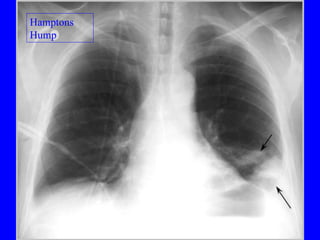

Pulmonary embolism (PE) is a common and potentially fatal condition where blood clots block arteries in the lungs. An estimated 5 million venous thromboses occur annually worldwide, with 10-30% of cases resulting in PE. Risk factors include immobilization, surgery, cancer, and estrogen use. Diagnosis involves assessing clinical probability based on symptoms and risk factors, followed by tests like D-dimer, chest imaging, ultrasound, V/Q scan, CT, or angiogram. Treatment aims to prevent further clotting with anticoagulants like heparin and warfarin, provide supportive care, and in some severe cases utilize thrombolysis or embolectomy.